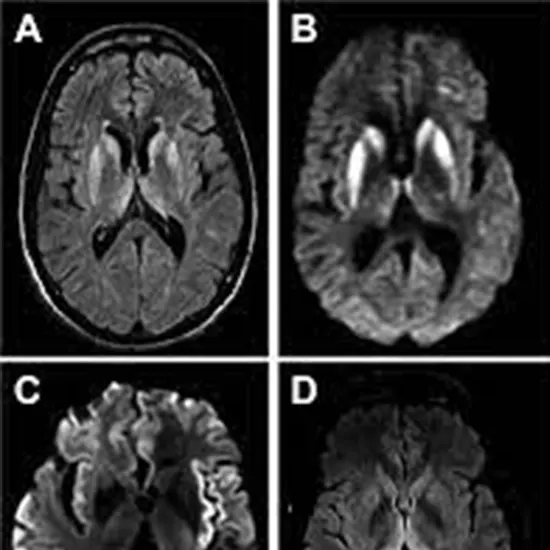

Jakob disease, also known as Creutzfeldt-Jakob disease (CJD), is a rare and fatal neurological disorder caused by abnormal proteins called prions that accumulate in the brain and cause damage to nerve cells. It belongs to a group of diseases known as transmissible spongiform encephalopathies (TSEs), which also include variant CJD (vCJD), kuru, and scrapie.

Jakob's disease can occur spontaneously, or it can be inherited in a small number of cases. It can also be acquired through exposure to infected tissue, such as contaminated medical equipment or tissues from infected animals. The symptoms of the disease can include rapid onset of dementia, difficulty with coordination and balance, muscle stiffness, and involuntary movements. The disease progresses rapidly, and patients usually die within a year of the onset of symptoms.

The diagnosis of both vCJD and classical/novel CJD is made through a combination of clinical evaluation, imaging studies, and laboratory tests, including analysis of cerebrospinal fluid and brain tissue.